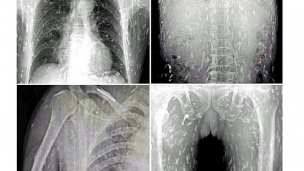

Dokter yang melakukan pemindaian pada tubuh pasien, menemukan kodisi horor: cacing pita memenuhi badan pria tersebut setelah ia kebanyakan makan sashimi -- makanan ala Jepang berupa irisan daging ikan mentah.

Dokter yakin, ikan mentah yang dikonsumsi penderita telah terkontaminasi. Pasien akhirnya dirawat di Guangzhou No. 8, Rumah Sakit Rakyat di Provinsi Guandong di China timur.

Sementara, Dr Yin dari Rumah Sakit Guangzhou No. 8 dalam situs that'smags.com mengatakan bahwa makanan yang terkontaminasi telur cacing pita bisa menyebabkan cysticercosis -- kondisi ketika cacing dewasa masuk ke aliran darah seseorang.

Tipe infeksi ini tak bisa dianggap remeh. Bisa mengancam jiwa seseorang, jika cacing mencapai otak manusia.